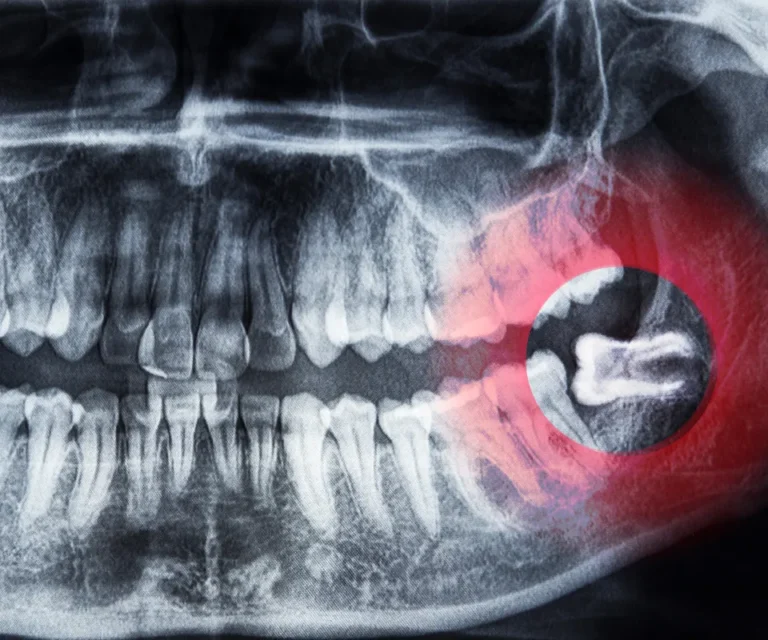

Wisdom Tooth Infection Emergencies

Wisdom teeth are especially prone to infection due to their position in the back of your mouth, making them harder to clean. Common signs of a wisdom tooth infection include:

Our emergency dentists in Newnan can assess whether you need antibiotics, drainage, or immediate extraction to eliminate infection and pain.

Diagnosis

A quick but thorough exam, including X-rays if necessary.